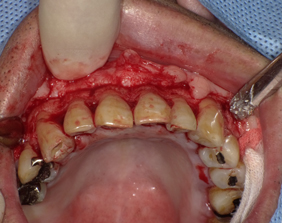

手術中

歯茎を切開して根の周りに付いていた歯石(歯肉縁下歯石)を全部取りました。